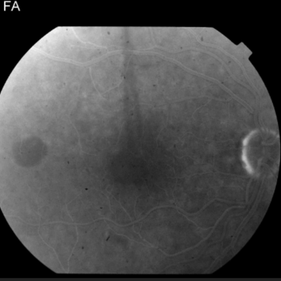

This 68 year old man was referred with a maculopathy but with normal visual acuity. He is thought to have multifocal Best Disease; there is no evidence of inflammation or uveitis and no history of cancer. Macular exam reveals yellow subretinal pigment clumping in each macula, including the foveal area. OCT shows moderate hyper-reflective PED, with no evidence of subretinal fluid or macular edema. Angiography reveals blocking defects due to pigment clumping with no evidence of CNVM.

Multifocal Best Disease Multifocal Best DiseaseJan 31 2015 by Thomas A. Ciulla, MD, MBA, FASRS Angiography reveals blocking defects due to pigment clumping with no evidence of CNVM. Photographer: Charlotte Harris Condition/keywords: adult vitelliform dystrophy, Best disease